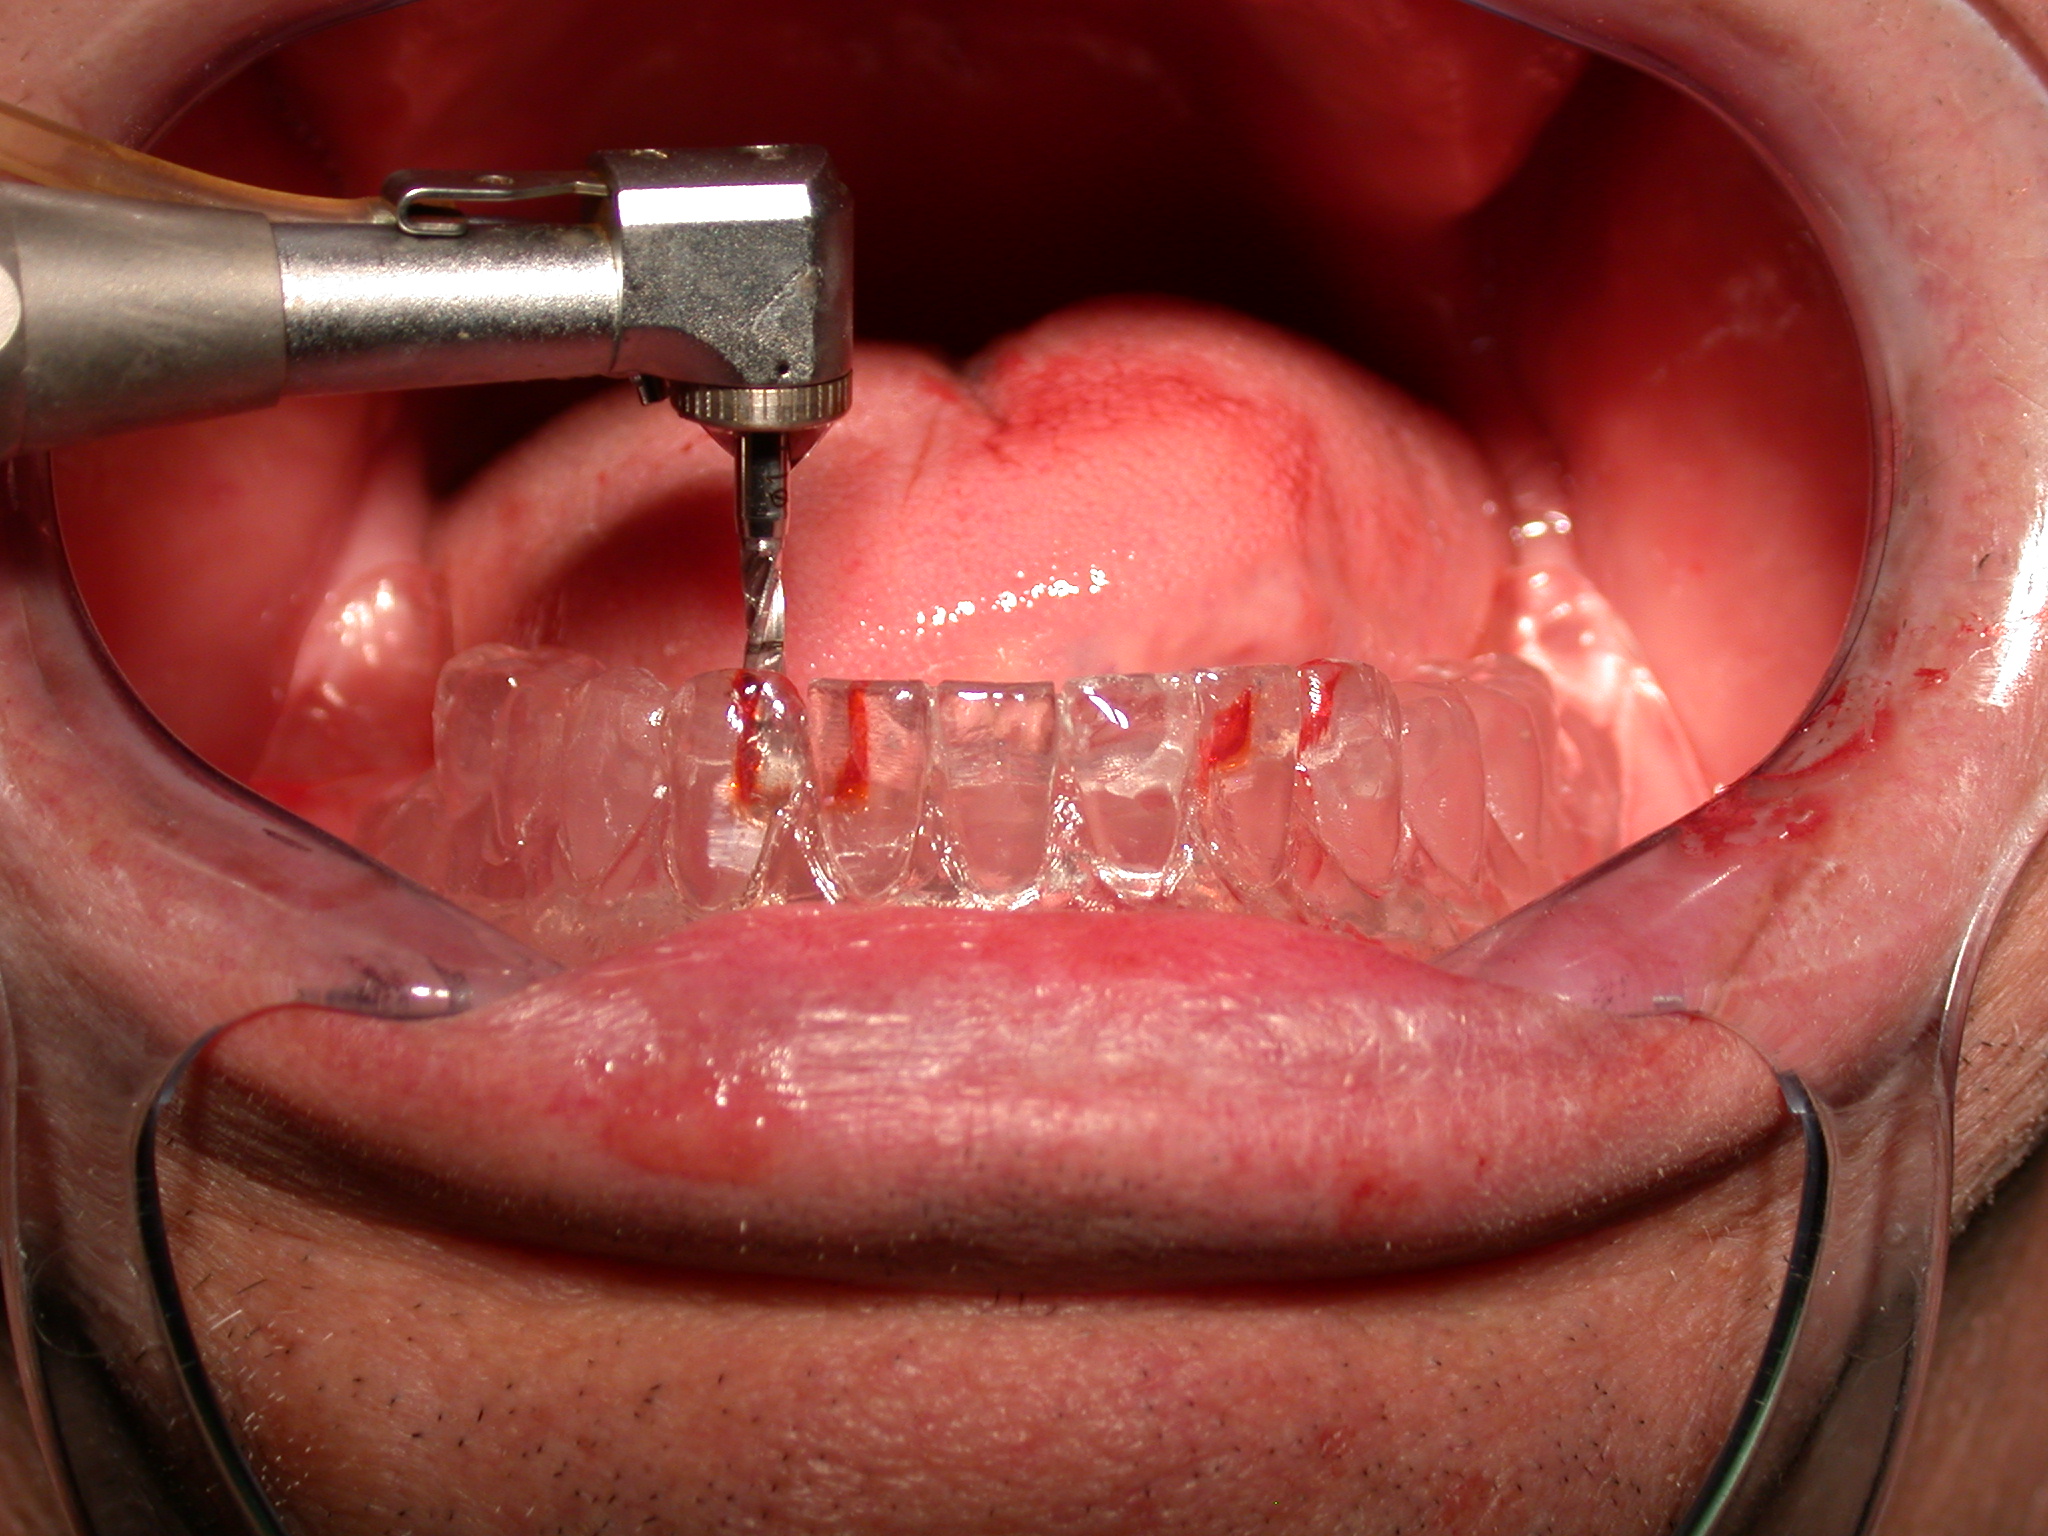

Diversi studi hanno dimostrato che le overdenture mandibolari supportate da impianti incrementano significativamente la soddisfazione e la qualità di vita dei pazienti edentuli. Il miglioramento della capacità di masticazione appare avere un impatto positivo sullo stato nutrizionale. In letteratura, solo pochi studi analizzano l’utilizzo dei mini impianti come supporto di overdenture mandibolari (Minifix - Prodent Italia - Pero, Milano).

Questo lavoro analizza l’utilizzo di overdenture supportate da mini impianti mandibolari posizionati nella zona interforaminale nel caso di atrofie gravi. Tutti i pazienti esaminati hanno mostrato soddisfazione su ciò che concerneva la ritenzione e la stabilità delle overdenture mandibolari.

Several studies have shown that implant supported overdentures in the mandible significantly increase satisfaction and quality of life in edentulous elderly patients. Improved chewing ability appears to have a positive impact on nutritional state. In dental literature there are only a few studies about overdenture supported by mini-implants. This study analysed mini-implant supported overdenture in the atrophic mandible of 2 patients. Both were satisfied with their overdentures that were judged stable and comfortable.